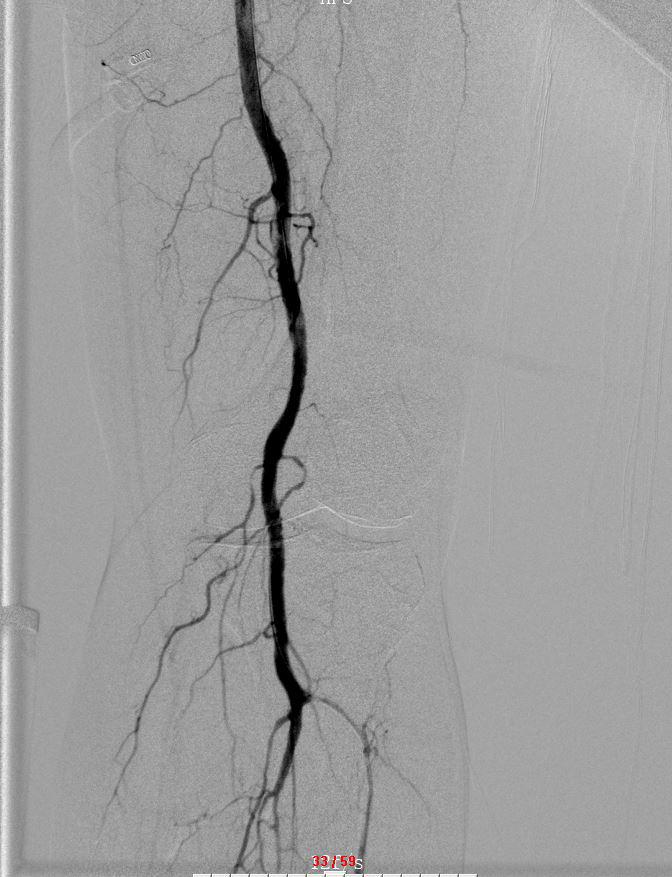

出院后,龙林主任指导团队为患者实施慢诊左下肢制影,左下肢浅动脉下段 + 腘动脉与栓、留置导管溶栓术,抽掏出 3~4 条蚯蚓大小的血栓。术后,患者下肢痛苦悲伤的情况明显好转。

" 招致他下肢动脉突收血栓的原因是房颤 ",龙林表示,房颤患者因为心净不克不及纪律跳动,所以随便构成血栓。为完全打点李嗲嗲的病症,龙林主任指导团队于 6 月 4 日再次为他实施左下肢动脉制影 + 左下肢动脉球囊扩大术,仅用一根 2.5 × 120mm 少的球囊导管便成功打通梗塞的血管。脚术耗时约 1.5 小时,术中几乎无出血,仅留下针眼大小的脚术创伤。